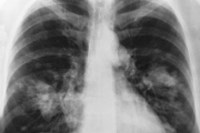

The study, led by scientists at The Institute of Cancer Research, London, showed how experimental drugs called PARP inhibitors could be useful in up to half of non-small-cell lung cancer (NSCLC) tumours with a fault in one of the ways cells repair damage to their DNA.

Lung cancer is the most common cause of cancer death in the UK accounting for more than a fifth of all cancer deaths. More than eight out of 10 cases of lung cancer are non-small-cell lung cancer - more than 33,000 cases per year in the UK.